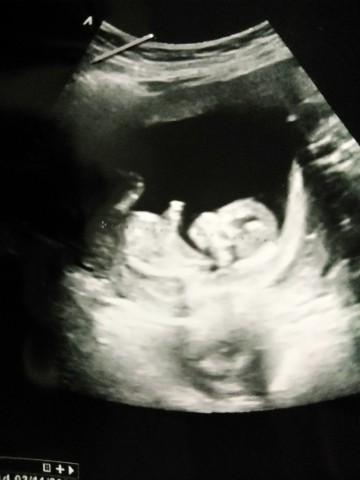

11 สัปดาห์ ซาวด์มาเจอลูกแบบนี้ถือว่าเขาตัวใหญ่ไหมคะหรือปกติ

บ้านนี้ตอน11w ค่ะ

บ้านนี้ตอน11wค่ะ